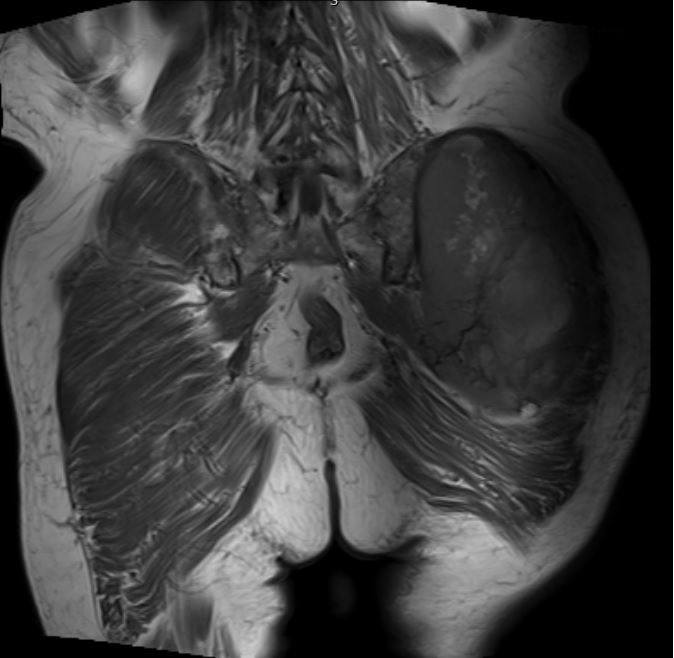

Fig. 1 & 2 Magnetic Resonance Image shows a large heterogeneous mass in the left gluteal region with low intensity signal on Axial (Fig. 1) and Coronal (Fig. 2) T1-weighted images admixed with some high signal areas indicative of fatty tissue. Higher intensity signal is visible compatible with hemorrhage or necrotic tissue. The mass involve the central portion of the left iliac bone.

Axial (Fig. 4) and Coronal (Fig. 5) contrasted T1-weighted MR images show a large heterogeneous mass with central and peripheral enhancement. Central low signal intensity image is compatible with necrosis and hemorrhage.

Fig. 6 STIR MR image demonstrates a large mass in the gluteal region with some enhancing tissue posterior to the trochanteric area which may reflect reactive edema.